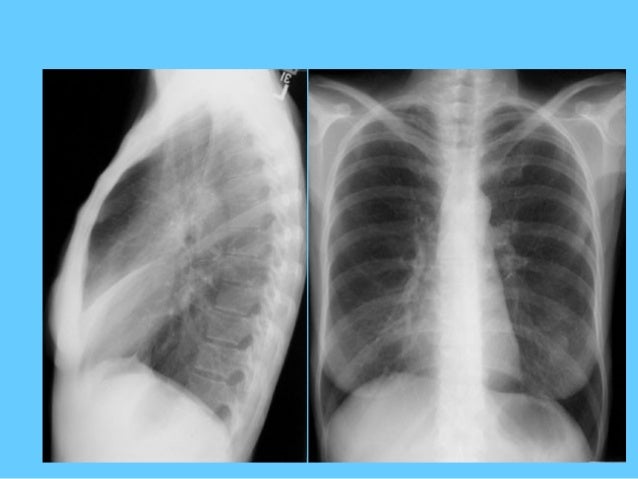

CHEST XRAY NORMAL VS ABNORMAL FREE

Normal vs abnormal ct chest images Abdominal Ultrasound | Cigna - Cigna, a Global Health Insurance.Ĭhest radiograph - Wikipedia, the free encyclopedia High resolution CT - Wikipedia, the free encyclopedia Cardiac CT, Coronary CT Angiography and Calcium Scoring High resolution CT - Wikipedia, the free encyclopedia Computerized Tomography (CT Scan, Computerized Axial Tomography or. folds, result from the presence of abnormal. Dynamic CT scan of chest during inspiration in normal patient. tomography (CT) scanning (see the images below). Lung Anatomy - Diseases & Conditions - Medscape Reference Many abnormalities can be detected on a chest X-ray. Normal Chest X-ray Test Abnormal Chest X-ray Test Chest X-ray Test Risks Obtaining Chest X-ray. Look for abnormal joints, bony lytic/blastic or soft tissue lesions.Ĭhest X-Ray Causes, Symptoms, Treatment - Abnormal Chest X-ray. Chest X-Ray Education (by topic) CT Imaging CT Dx of.Ĭhest X-ray - Brookside Associates Medical Education Division easily identify "abnormal" signs of active disease. What Abnormal.ġ00 Normal Chest X-Rays - Perelman School of Medicine at the.ġ00 Normal Chest X-Rays. result means your chest area appears normal.

previous x-rays or CT scans Diagnose abnormal growths in the chest. Erect posterior-anterior ("PA") chest radiograph PA images commonly show.Ĭhest MRI: MedlinePlus Medical Encyclopedia Image finding: Normal chest PA film, case 2. Yale: Cardiothoracic Imaging - Image finding: Normal chest PA film. After a CT exam, you can return to your normal activities. Chest CT scans.ĬAT Scan (CT) - Chest - RadiologyInfo - The radiology information.Ī low-dose chest CT produces images of sufficient image quality to detect many lung diseases. areas in your chest, which helps create clearer images. What Is a Chest CT Scan? - NHLBI, NIH - NIH Heart, Lung and Blood.Ī chest computed tomography (to-MOG-ra-fee. Chest CT CT scan - lungs CT scan - chest. and uses it to create several individual images. Thoracic CT (computer tomography) is an imaging method that. Thoracic CT: MedlinePlus Medical Encyclopedia A CT 'slice' through the chest shows normal. Normal CT scan of the chest of a 9-year-old boy. Radiology images and videos for Computed Tomography (CT) - Chest. Images and Videos - Computed Tomography (CT) - Chest